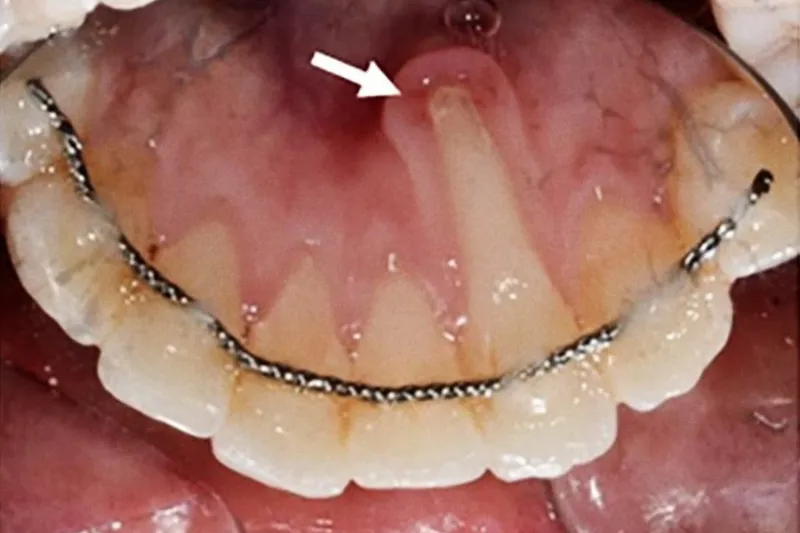

Patientskader er en komplikation, som kan opstå i forbindelse med enhver form for sundhedsfaglig behandling. Patientskader anses som en uundgåelig del af sundhedssystemet og dermed også det odontologiske behandlingstilbud. Når disse opstår, kan det have både individuelle, sociale, samfundsmæssige og økonomiske konsekvenser. Der er et stigende internationalt fokus på patientsikkerhed og skader i forbindelse med behandlinger i sundhedsvæsnet. Den nærværende artikel har til hensigt at belyse typer af patientskader, som kan opstå i forbindelse med ortodontiske behandlingsforløb – som ortodonti praktiseres i privat tandplejeregi i Danmark. Skader relateret til ortodontisk behandling kan omfatte skader på tandvæv, den omkringliggende knogle og blødtvæv samt påvirkning af den orofaciale funktion. Desuden kan en skade opstå efter afsluttet tandregulering (recidiv) eller på grund af manglende diagnostik og rettidig igangsættelse af behandling. Ikke to patientskader er ens, og ofte er der tale om et komplekst samspil mellem forskellige bidragende faktorer. Patienter, der er udsat for en skade, har ret til at modtage information omkring forløbet, så disse kan danne sig et samlet overblik over skadesforløbet. Fokus på patientsikkerhed og patientskader er af stor interesse for patienter, såvel som det sundhedsfaglige system i Danmark.

Although patient safety has been well established in other disciplines, it is still in its infancy in dentistry and especially orthodontics. This article aims to describe the different types of patient harms related to orthodontic treatment and highlight causes that may contribute to their occurrence. Patient harm in orthodontics include damage to the dental tissues (root resorption, enamel demineralization, hypersensitivity), periodontal damage (gingival recessions, bone loss), allergies, negative impact on orofacial function, relapse, deficient or late diagnosis and emotional damage. No two patient injuries are the same. It often is a complex network of multiple contributing factors and not as a result of a single causal factor. Patient harm often has a significant impact on the parties involved. Nevertheless, concrete protocols to avoid patient safety incidents in orthodontics are lacking. When an adverse event occurs and a patient is exposed to harm, all the necessary steps to minimize the extent of the injury need to be taken. Also, the patients are entitled to receive open and honest information about the course of events, so that they can form an overall picture of the course of the injury. Research is needed in the field of patient safety in Orthodontics by identifying the different types of patient harm, as well as the contributing factors that lead to these adverse events. This is of great interest to patients as well as the healthcare system in Denmark.